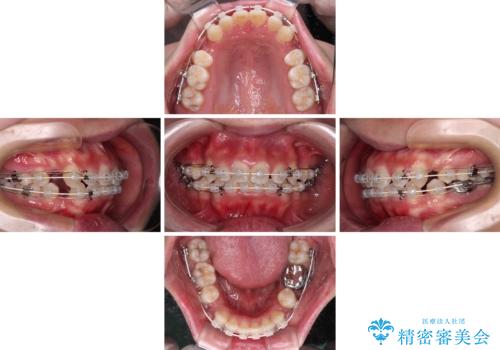

- 矯正装置

- 審美装置

- 前歯のデコボコやクロスバイト、口元の突出感を気にして来院された患者様です。

上下左右の第一小臼歯4本を抜歯して、ワイヤー装置にて矯正治療を行うこととしました。